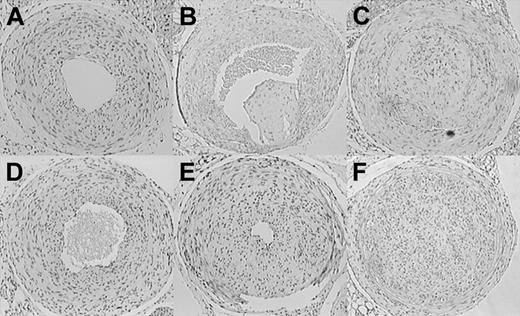

The effect of hyperfibrinogenemia on stasis-induced thrombus formation was investigated by employing an established experimental protocol that reduces blood flow in the common carotid artery to a residual, pulsatile mode and induces reproducible alterations of arterial wall function by a combination of neointimal hyperplasia and vascular remodeling.26,29 The model is distinguished by the continued presence of a functional endothelium and in animals with normal coagulation systems produces little thrombosis that remains limited to the site of the ligation.26,30 Of 12 wild-type mice analyzed, none showed evidence of organized thrombus formation. The incidence of neointima formation was 8/12 in this control group, and all of the ligated vessels had maintained lumen patency (Figure 6A). As shown previously, when applied to hypercoagulable TMPro mice, carotid artery ligation elicits extensive and persistent thrombotic occlusion with subsequent remodeling and thrombus organization.21 These findings were reproduced here in a group of 5 TMPro animals, all of which showed clear evidence of organized thrombi (Figure 6B-C). Two independent control experiments on fibrinogen-deficient animals (n = 6 and 8, respectively) showed that the absence of fibrinogen does not prevent neointimal hyperplasia/vascular remodeling associated with this experimental model (Figure 6D). Intimal hyperplasia was documented in 8 of 12 Hifib mice (Figure 6E). Morphometric analysis of serial sections derived from the ligated arteries showed that hyperfibrinogenemic mice, in comparison to wild-type mice, exhibited significantly reduced cross-sectional lumen area (387 ± 223 versus 499 ± 145 area units ± SD; P < .05). The extent of intimal hyperplasia was greater in Hifib mice (495 ± 394 versus 240 ± 134 area units ± SD; P < .05). All other parameters measured (length of internal and external elastic lamina, vessel circumference, medial area, intimal cell density) were not significantly different between Hifib mice and controls. Likewise, the morphology of the unligated carotid artery was identical in both groups. In 3 of 12 Hifib carotid arteries the lumen was completely replaced by cellular tissue along the entire length of the carotid from the site of the ligation to within a short distance from the aortic arch (Figure 6F). In general, the morphology of the lesions in Hifib mice differed from that seen in prothrombotic TMPro mice. In particular, we noted the absence of irregular tissue fragments in the lumen or in association with segments of the intima, which are characteristic features of the occlusions/organized thrombi in TMPro animals (compare Figure 6C and 6F). In contrast, the ligated carotid artery of Hifib mice resembled the appearance of the nonthrombotic vascular wall of ligated wild-type vessels, consistent with a minimal degree of thrombosis. Ligation of the carotid artery did not alter the plasma concentration of fibrinogen, TAT-complex, D-dimer, or interleukin-6 in this control group, as compared to sham-operated animals (measured at 7, 14, 21, and 28 days after injury; data not shown).

Stasis-induced thrombosis and vascular remodeling in the carotid artery of mutant mice. Representative sections through the ligated carotid artery of mutant mice, obtained 4 weeks after ligation. H&E staining, cell nuclei appear dark. Neointima formation but no thrombosis in wild-type (A) and fibrinogen-deficient (D) mice. Neointima formation and severe thrombosis in thrombomodulin-deficient mice (B-C). Enhanced (E) and in some cases occlusive stenosis/intimal hyperplasia in hyperfibrinogenemic mice (F). Note the absence of organized thrombi in Hifib animals. Original magnification, × 40.

These data show that preexisting hyperfibrinogenemia does not elicit thrombosis in excess of that seen in wild-type animals or alter the incidence of neointima formation in this model. On the other hand, hyperfibrinogenemia modified vascular remodeling elicited by cessation of blood flow, resulting in augmented intimal hyperplasia and narrowing of the vessel lumen.